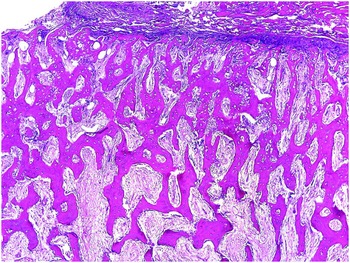

61g3pHBqBoL._AC_UF1000,, Diagnosis of bone and joint disorders : Resnick, Donald,

Diagnosis of bone and joint disorders : Resnick, Donald, Diagnosis of Bone and Joint Disorders: Resnick, Donald,

Diagnosis of Bone and Joint Disorders: Resnick, Donald, Diagnosis of Bone and Joint Disorders: Resnick, Donald,

Diagnosis of Bone and Joint Disorders: Resnick, Donald, 61sa2nN44qL.jpg,

61sa2nN44qL.jpg, fendo-13-819641-g001.jpg,

fendo-13-819641-g001.jpg, Diagnosing bone disease (Chapter 1) - Pathology of Bone and,

Diagnosing bone disease (Chapter 1) - Pathology of Bone and, Diagnosis of Joint Disorders | SpringerLink,